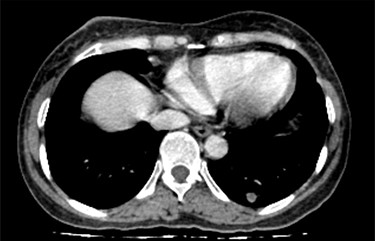

CT scan of the chest revealed a large tumor involved whole right breast tissue (Fig. 1), bilateral pulmonary metastasis without mediastinal adenopathy (Fig. 2) and axillary lymph node enlargement measuring 1.5 cm with central necrosis.